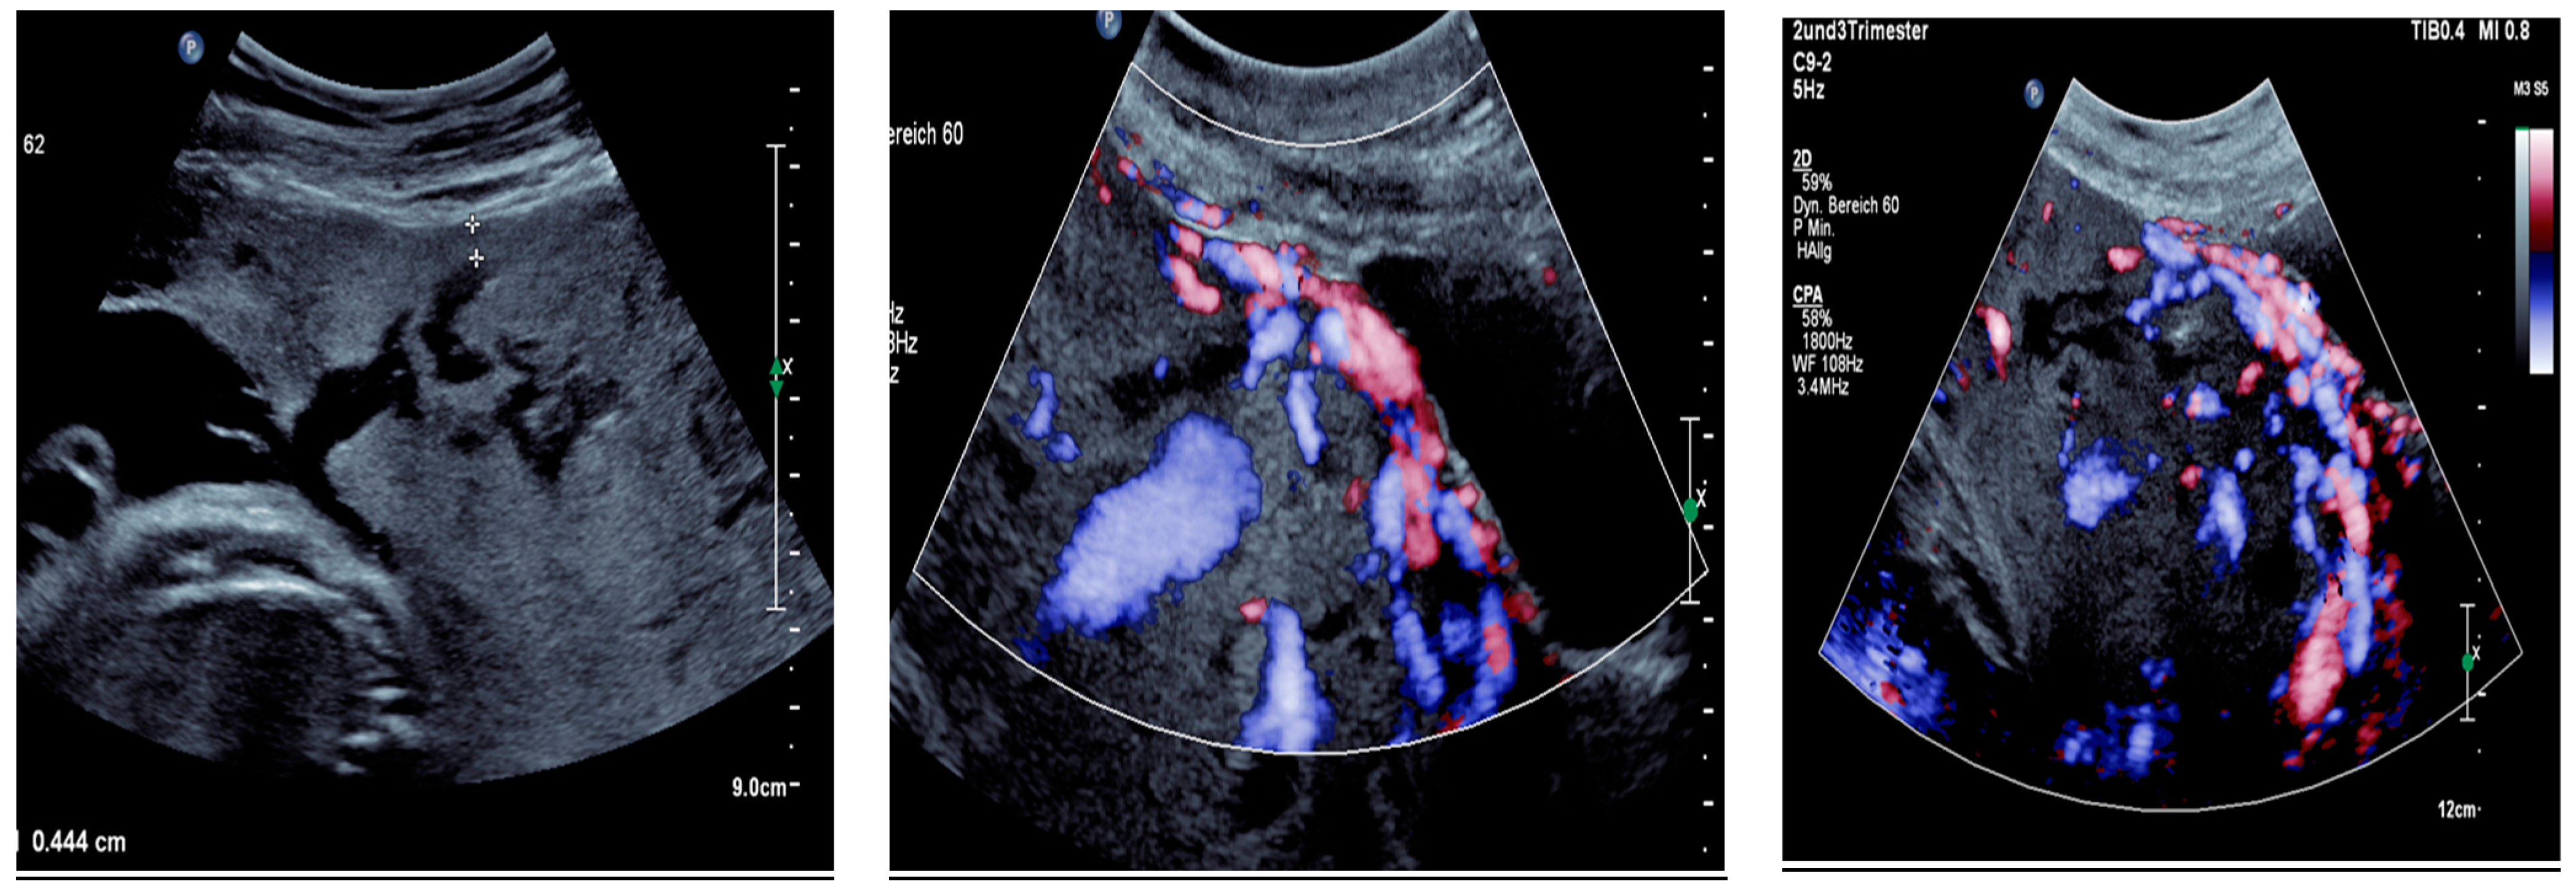

Sonographic findings (Figure 9):

Figure 9.

Irregular, large lacunae within the placenta, Hypervascularity, Turbulent flow inside the lacunae Diameter gaps.